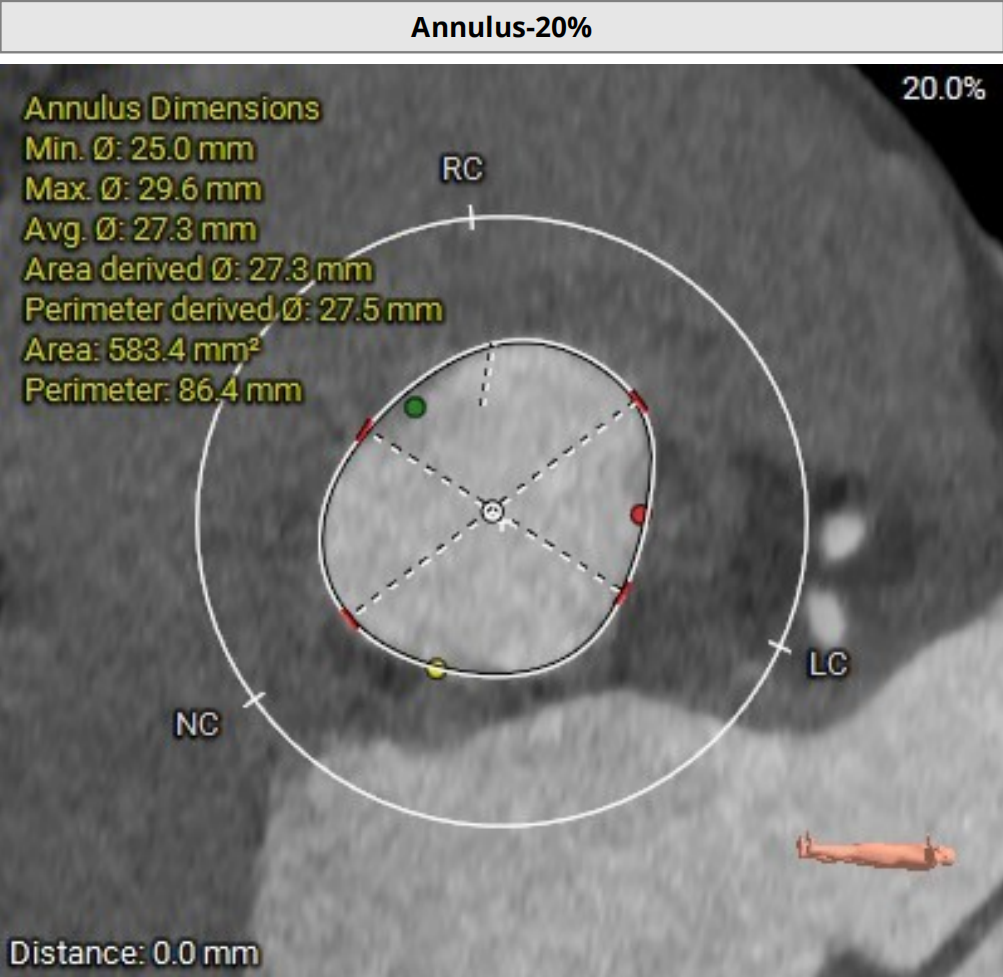

2026年伊始,TaurusTrio经导管主动脉瓣系统在复旦大学附属中山医院,浙江大学医学院附属第二医院,中国医学科学院阜外医院,首都医科大学附属北京安贞医院,四川大学华西医院等多家临床中心成功开展上市后全国首批植入。这不仅是TaurusTrio正式走向广泛临床应用的重要里程碑,更标志着中国单纯主动脉瓣反流介入治疗正式迈入了“心键合璧”的全新纪元。